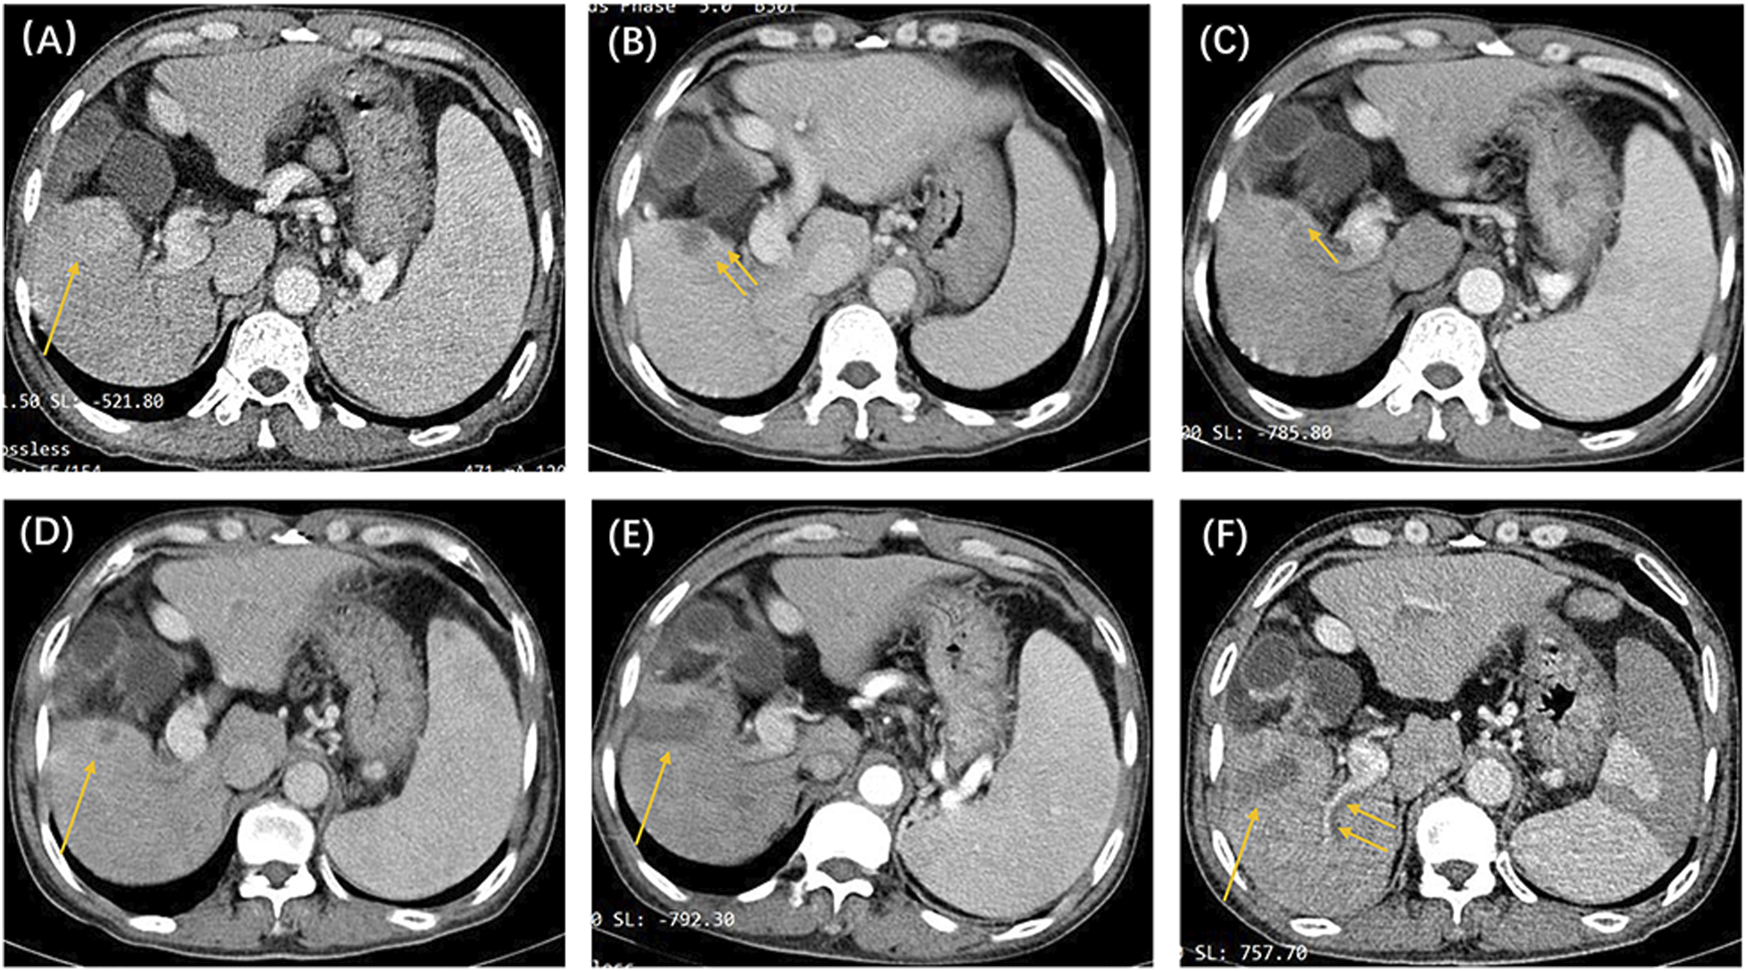

In this study, we identified 109 patients with HCC with BCLC stage A or B who initially underwent the DEB-TACE procedure at our hospital. After excluding 16 patients who did not meet the inclusion criteria, 93 patients were finally included in the study (Figure 1). Table 2 shows the baseline clinical and radiologic information of patients. The median follow-up period was 958 days (95% CI: 757–1,159). Based on the definition of UP, 77 (82.8%) patients developed UP; among them, 42 (54.5%) developed multiple intrahepatic nodules following treatment, and subsequent locoregional interventional therapy failed to induce tumor remission; 11 (14.3%) developed extrahepatic metastasis; 3 (3.9%) maintained SD after two continuous interventions (Figure 2); 13 (16.9%) developed vascular invasion (Figure 3); 2 (2.6%) had hepatic function progress from grade A or B to grade C; and 6 (7.8%) patients had primary tumor enlargement by >20%, and subsequent locoregional interventional therapy did not induce tumor remission.

FIGURE 3

The patient was a 53-year-old man, with a clinical diagnosis of hepatocellular carcinoma, Barcelona Clinic Liver Cancer stage A, and pre-treatment hepatic function of the Child–Pugh grade (A). The above shows the contrast-enhanced CT images before and after locoregional interventional therapy. (A) Image taken before the initial drug-eluting beads–transcatheter arterial chemoembolization treatment, showing that the right lower liver lobe is full of blood-supplying, space-occupying lesions (single arrow). (B) Image taken 6 weeks after the initial TACE procedure. Suspicious nodular enhancement lesions could be seen around the target tumor (double arrows). The target tumor was assessed to be partial response based on modified response evaluation criteria in solid tumors (m-RECIST) criteria. (C) CT image 8 weeks after the second TACE procedure. Suspected annular enhancement was still seen at the margin (single arrow). The target tumor was assessed to be stable disease based on m-RECIST criteria. (D) Periodic image review 16 weeks after the second TACE procedure. Marginal enhancement and suspected recurrence (single arrow) could be seen. Tumor microwave ablation was performed under CT guidance. (E) Image taken 6 weeks after the ablation procedure. The target tumor was assessed to be complete response (single arrow) based on m-RECIST criteria. (F) Periodic image review 14 weeks after ablation. The filling defect seen in the right hepatic portal vein branch (double arrow) was considered to be a vascular invasion. According to the untreatable progression (UP) criteria, the patient was ultimately deemed to have UP.